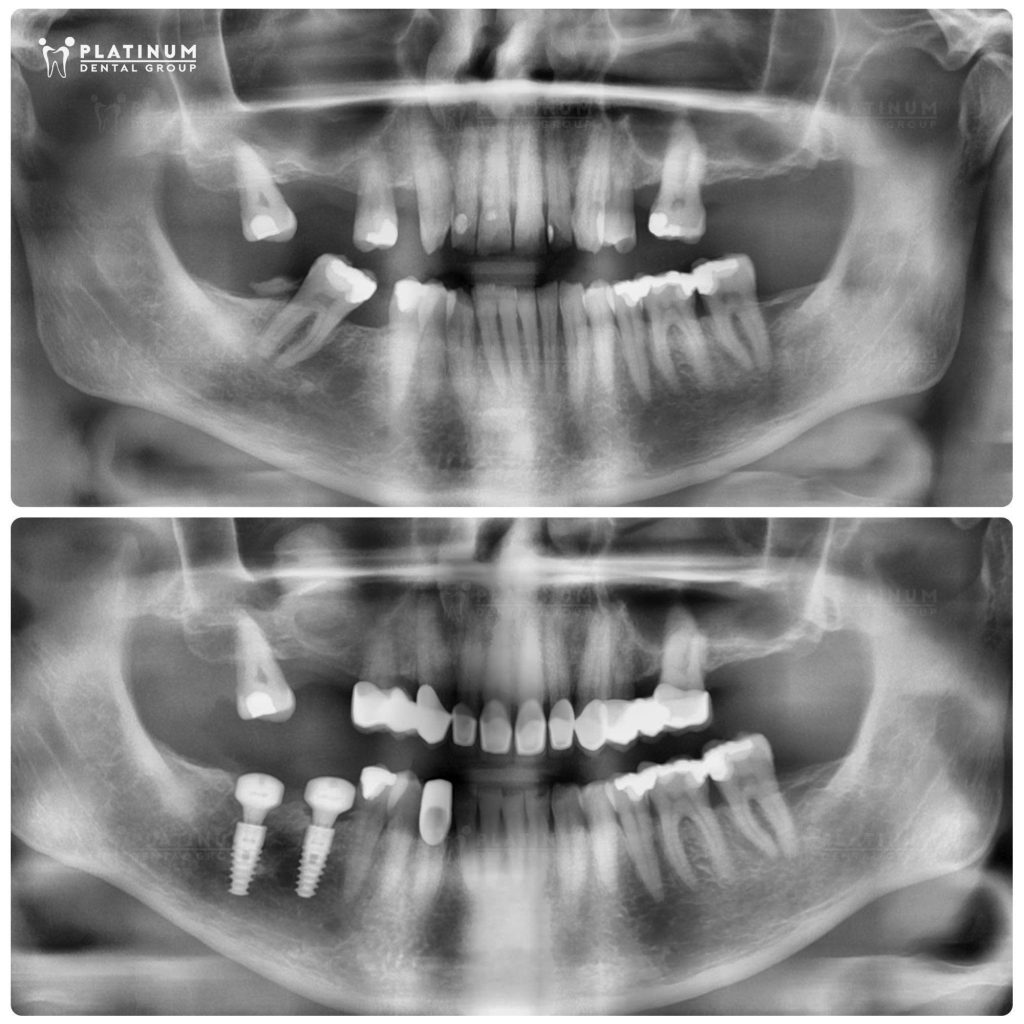

Lộ trình điều trị bắt đầu với cấy ghép Implant do Bác sĩ Dương Minh Tùng thực hiện. Các điều trị gồm có nâng xoang, ghép xương và trồng Implant tại vùng răng hàm đã mất.

Bác sĩ Quốc Duy thực hiện phục hình mão sứ cho các răng sâu, vỡ mẻ lớn của hàm trên đồng thời cân chỉnh lại cung cười.

Toàn bộ quá trình được lên kế hoạch chặt chẽ ngay từ đầu, đảm bảo sự tương trợ giữa Implant và phục hình sứ, từ đó giúp tái lập khớp cắn ở trạng thái ổn định, thoải mái và bền vững lâu dài.